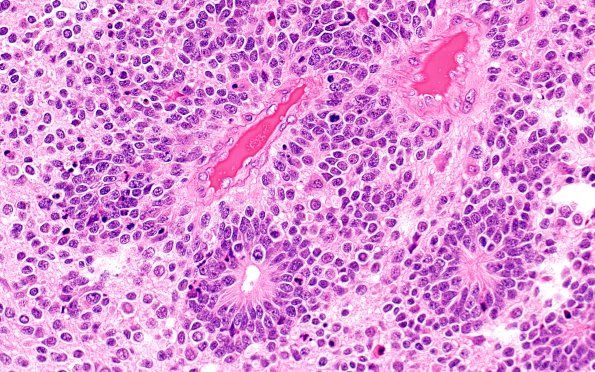

Washington University Experience | NEOPLASMS (EMBRYONAL) | ETMR - Embryonal Tumor Multilayered Rosettes | 8B5 ETMR (Case 8) B1 H&E 40X 1

Other patterns include a minor population of perivascular pseudorosette and neuroblastic forms as well as true rosettes. (H&E)